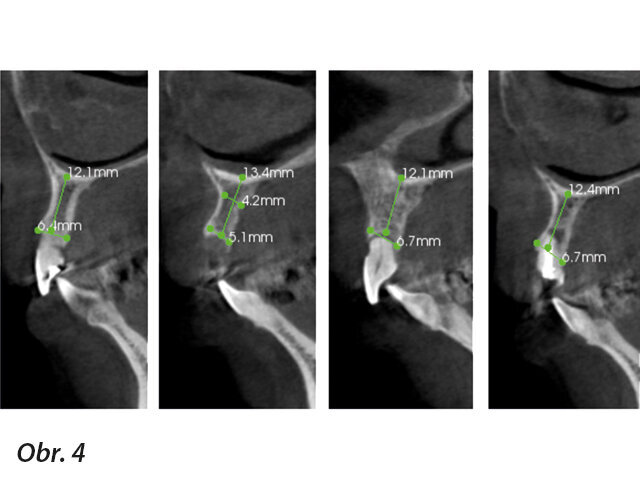

Na naše pracoviště se dostavila čtyřicetiletá pacientka, která před třemi týdny následkem synkopy utrpěla úraz horních frontálních zubů. Při klinickém vyšetření jsme diagnostikovali avulzi zubu 11 a korunky zubů 12 a 21 byly ulomené 3–5 mm pod úrovní gingivy s mobilitou III. stupně. Dále jsme zjistili zlomeninu korunky zubu 22 s lomnou linií končící ekvigingiválně. Ostatní zuby nevykazovaly žádné zjevné patologie či abnormality (obr. 1–4). Po vyloučení celkových onemocnění jsme se rozhodli pro ošetření pomocí implantátů s důrazem na estetiku a funkci.